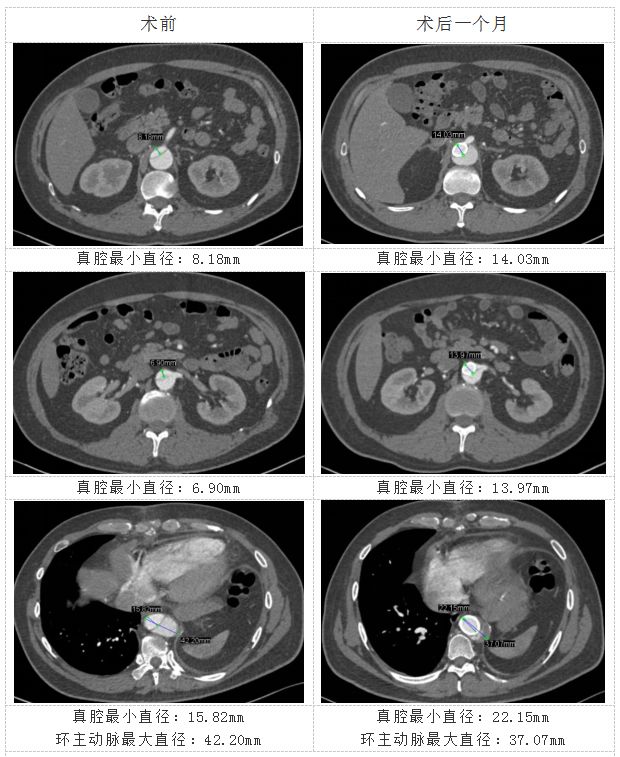

目前,患者行术后1月随访发现,所有重要分支均保持通畅,主动脉真腔明显扩大,环主动脉最大直径缩减(图1)。

图2 主动脉真腔明显扩大,环主动脉最大直径缩减

CTA检查显示主动脉假腔进行性血栓形成;假腔体积由术前的103立方厘米缩减至术后的74立方厘米,减少幅度达28%(图3)。

图3 术后假腔体积较术前减小28%